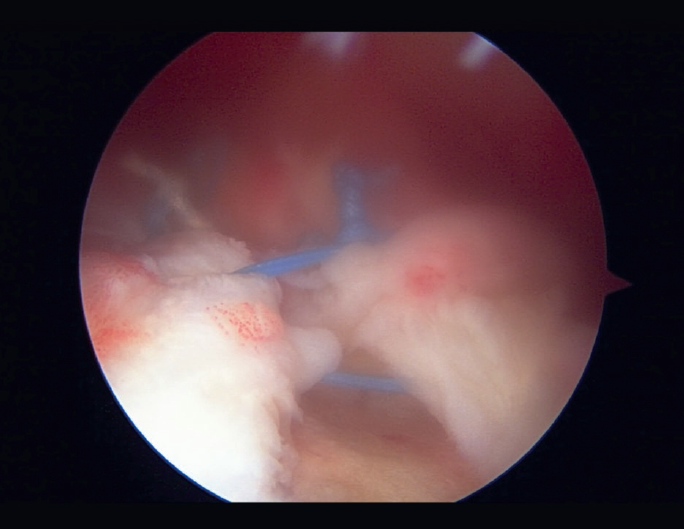

Arthroscopic partial repair was introduced by Burkhart(19) in 1994, who described the technique for restoring torque and the "suspension bridge" system of the shoulder. Understanding this concept is crucial for optimizing this type of repair (Figure 1).

The suspension bridge system was also described by Burkhart(20). In the arthroscopic view, the most distal portion of the cuff insertion has a half-moon or semicircular shape, and there are a series of thick fiber bundles at its margins that lie perpendicular to the axis of the tendon of the supraspinatus, arching from the anterior to the posterior zone to join with the humerus - an element known as the rotator cable.

In their study, Burkhart et al.(20) demonstrated that the majority of ruptures occurred more through the soft tissues than in the rotator cable, and if the latter was not affected, rupture would not be expected to extend either anteriorly or posteriorly. They found the location of rupture to be more important than its size, since a lesion involving the rotator cable is biomechanically more significant than rupture in the semicircular zone.

The relevance of this study is based on distinguishing anatomical integrity from biomechanical integrity. The partial repair procedures in massive ruptures are based on this biomechanical concept, on repair of the rotator cable.

The concept of "functional rupture of the rotator cuff" refers to an anatomically deficient but biomechanically intact cuff, i.e., a patient with functional rupture has normal function despite tendon disruption. Based on this, there are selected cases of massive rupture in which partial repair may prove useful.

The aim of partial repair is to recreate functional rupture of the rotator cuff, and this could be achieved if we are able to repair at least the lower half of the infraspinatus(19)(Figure 2).